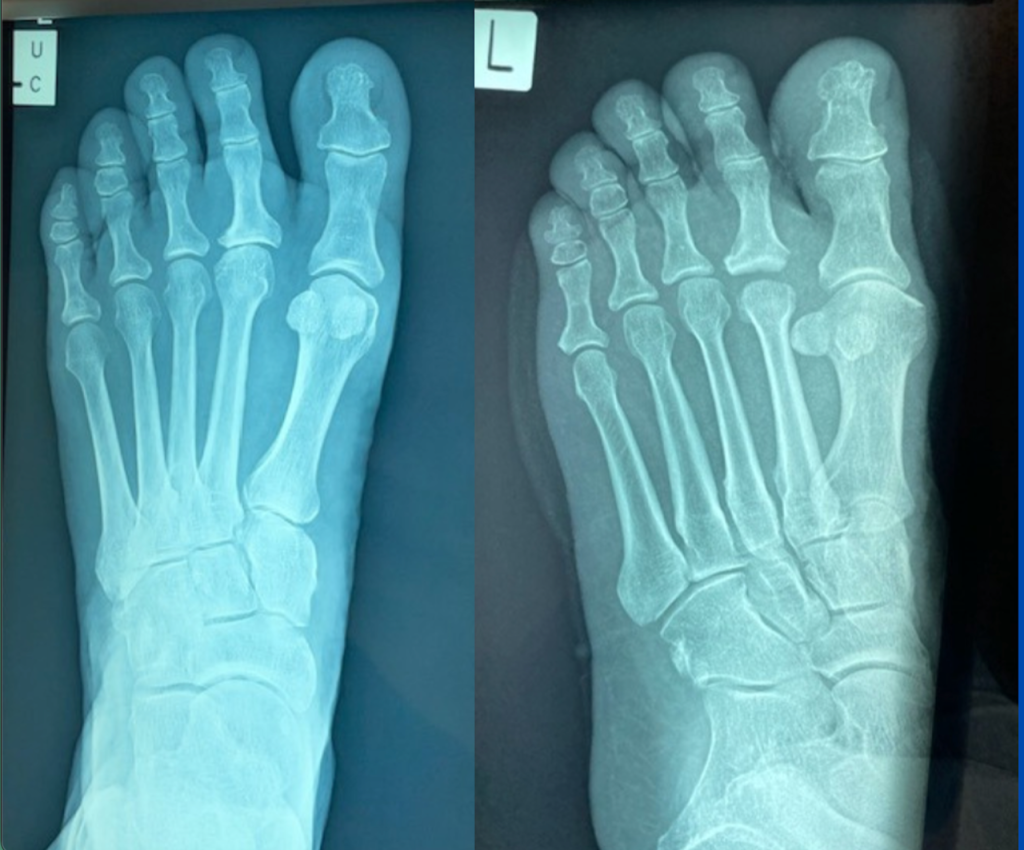

Blog's main page This 16-year-old had been struggling since he commenced walking – marked and multiple symptoms on the foot, including lateral midfoot and rearfoot pain, and bunion formation. However, his main symptoms were being experienced on the medial longitudinal arch. The non-weight-bearing image was taken on the day of his surgery, but, when he first [...]